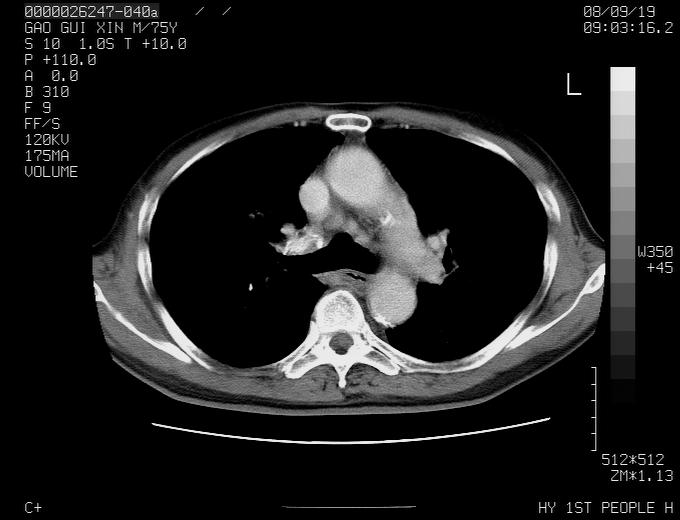

右上肺可见条索状影,并可见钙化,左上肺结节可以考虑为结核球,但气管前腔静脉后有肿大淋巴结,本人觉得左上肺结节不能排除转移瘤的可能,右上肺为陈旧性结核灶。

左肺上叶周围性肺癌并纵隔多组lnm.不可能是tb.

左肺上叶尖段瘢痕癌并纵隔淋巴结转移解释更好一些.

左肺周围癌并纵隔淋巴结转移,另一小结节是血管影

别再ct讨论了,一个纤支镜检查马上明确.肺癌不会错的!应该是低分化鳞癌.

左上肺周围型肺癌并纵隔淋巴结转移

1)左肺上叶尖段周围型肺癌并纵隔淋巴结转移。2)冠状动脉及主动脉钙化。

左上肺周围型肺癌并纵隔淋巴结转移。纤支镜检查